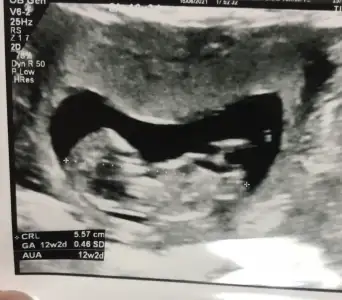

Erkek görünüyorMERHABA İyi Akşamlar,12 hafta ultrason görüntüsü bana da tahminde bulunabilirseniz çok Sevinirim![]()

Erkek görünüyor

Çok teşekkürlerErkek görünüyor